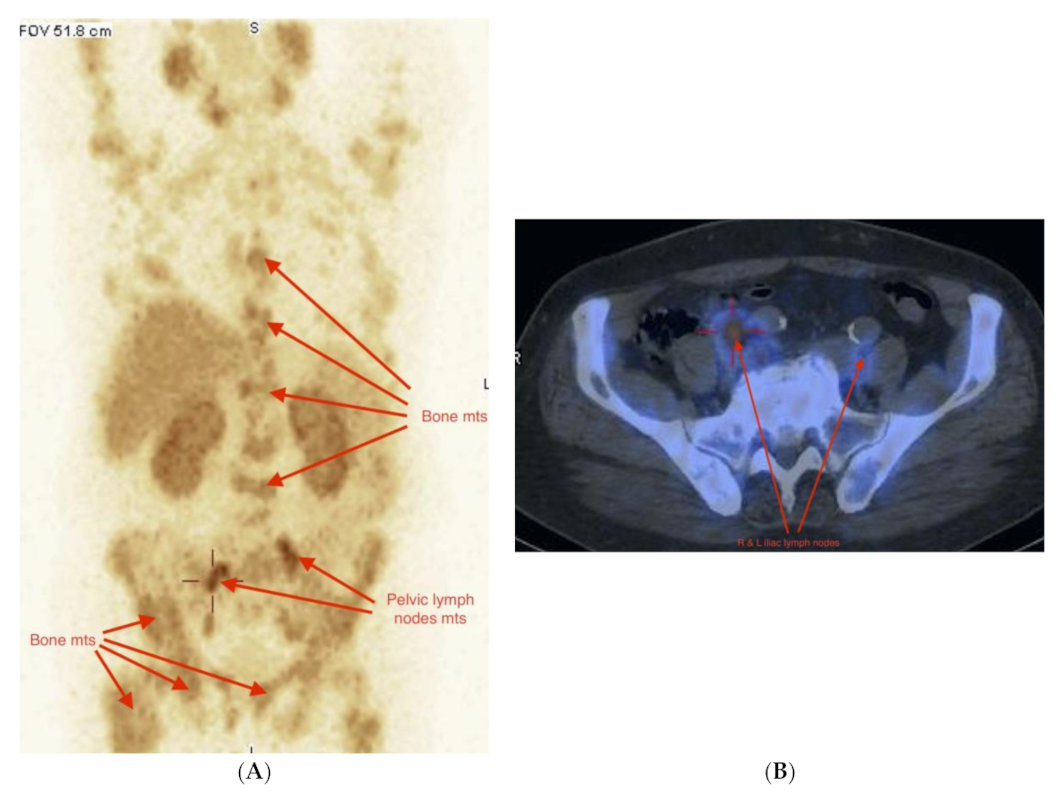

2.3. Imaging Studies

2.4. Detection of Active Pathology in Patients